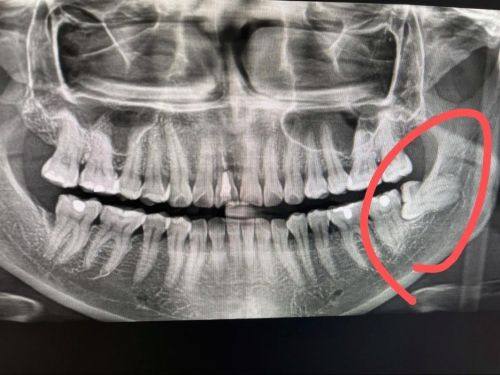

郑州植美口腔科下颌阻生智齿拔除:800元起